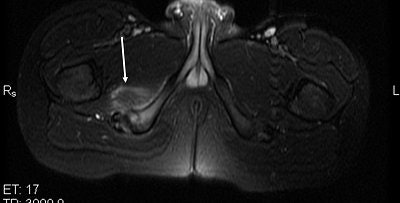

![]() |

| Figure 2. Axial T2-weighted MR image of the pelvis shows increased signal within the soft tissue adjacent to the right ischial tuberosity (white arrows). |